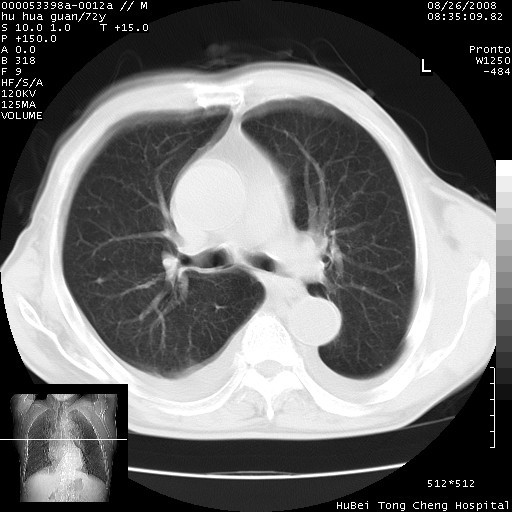

标题: CT15582:M,72Y。请老师帮分析胸部病变。

可以明确的说。肯定不是主动脉夹层破裂出血!考虑为淋巴瘤或间叶组织来源的恶性肿瘤可能性大。右肺小结节建议薄层观察,如能发现恶性征象,那椎前改变就考虑为转移所致。至于双侧少量胸水乃静脉血回流受阻所致。

1、右肺周围性肺癌、胸腔积液(双)

1、右上肺结节病变,肺泡癌不除外,请随诊;左下肺近后纵隔病变,考虑纵隔型肺癌侵犯大血管可能;

2、右下肺背段少许炎症,双侧胸腔积液,右下肺纤维索条。

降主动脉前移位,后纵隔占位

后纵隔占位,降主动脉前移位;双侧胸腔积液;应排外食管病变侵犯血管可能;

建议排除结核引起的冷脓肿。